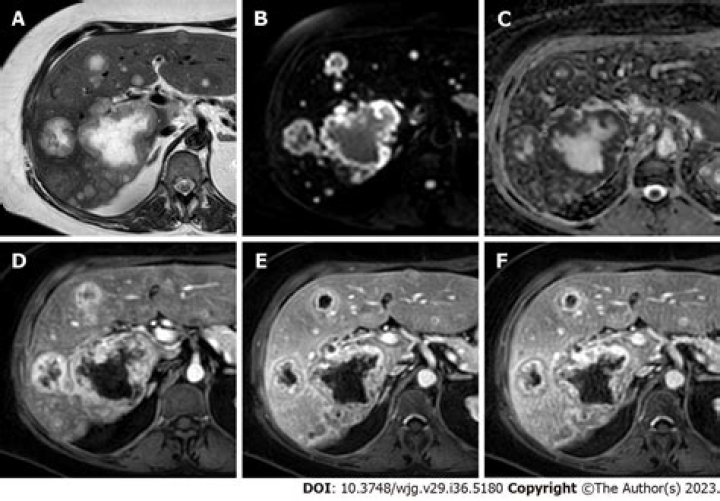

Where does RCC metastasis to?